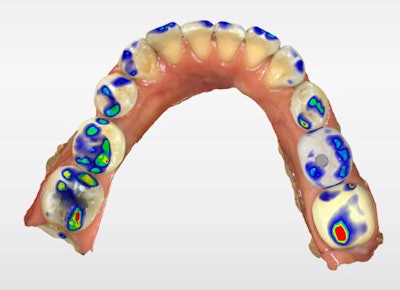

The definitive crown was then designed in CEREC software (Figure 4) using virtual articulation and occlusal analysis (Figure 5) and verified in a full-arch digital view for occlusal harmony (Figure 6). Milling was completed using CEREC Primemill with a Katana Zirconia One for Implant block, producing excellent marginal adaptation and lifelike translucency (Figure 7).

Figure 5: Virtual articulation and occlusal analysis.

Figure 6: Full-arch digital verification.